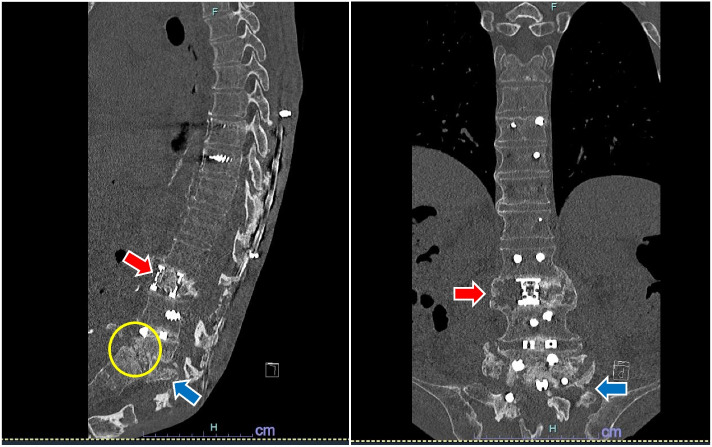

Case presentation: We report the anesthetic management of a 76-year-old man with PD who developed severe long-seated forward flexion with the face buried between the knees, from camptocormia and multiple spinal surgeries. Removal of the exposed spinal implants was necessary, and general anesthesia was planned. Anesthesia was administered in the right lateral position from induction to awakening. Video laryngoscopy enabled successful intubation, and remimazolam with flumazenil ensured good recovery without complications.